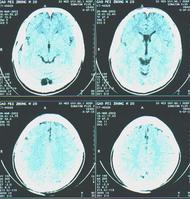

1、患兒腦部CT和MRI檢查